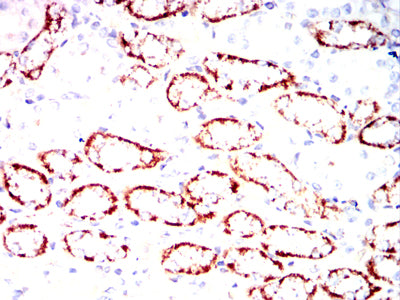

- Immunohistochemical analysis of paraffin-embedded mouse kidney tissues using ZP2 mouse mAb with DAB staining.

- Immunohistochemical analysis of paraffin-embedded Rat kidney tissues using ZP2 mouse mAb with DAB staining.